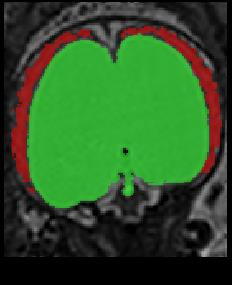

Limiting failures of machine learning systems is of paramount importance for safety-critical applications. In order to improve the robustness of machine learning systems, Distributionally Robust Optimization (DRO) has been proposed as a generalization of Empirical Risk Minimization (ERM). However, its use in deep learning has been severely restricted due to the relative inefficiency of the optimizers available for DRO in comparison to the wide-spread variants of Stochastic Gradient Descent (SGD) optimizers for ERM. We propose SGD with hardness weighted sampling, a principled and efficient optimization method for DRO in machine learning that is particularly suited in the context of deep learning. Similar to a hard example mining strategy in practice, the proposed algorithm is straightforward to implement and computationally as efficient as SGD-based optimizers used for deep learning, requiring minimal overhead computation. In contrast to typical ad hoc hard mining approaches, we prove the convergence of our DRO algorithm for over-parameterized deep learning networks with ReLU activation and a finite number of layers and parameters. Our experiments on fetal brain 3D MRI segmentation and brain tumor segmentation in MRI demonstrate the feasibility and the usefulness of our approach. Using our hardness weighted sampling for training a state-of-the-art deep learning pipeline leads to improved robustness to anatomical variabilities in automatic fetal brain 3D MRI segmentation using deep learning and to improved robustness to the image protocol variations in brain tumor segmentation. Our code is available at https://github.com/LucasFidon/HardnessWeightedSampler.